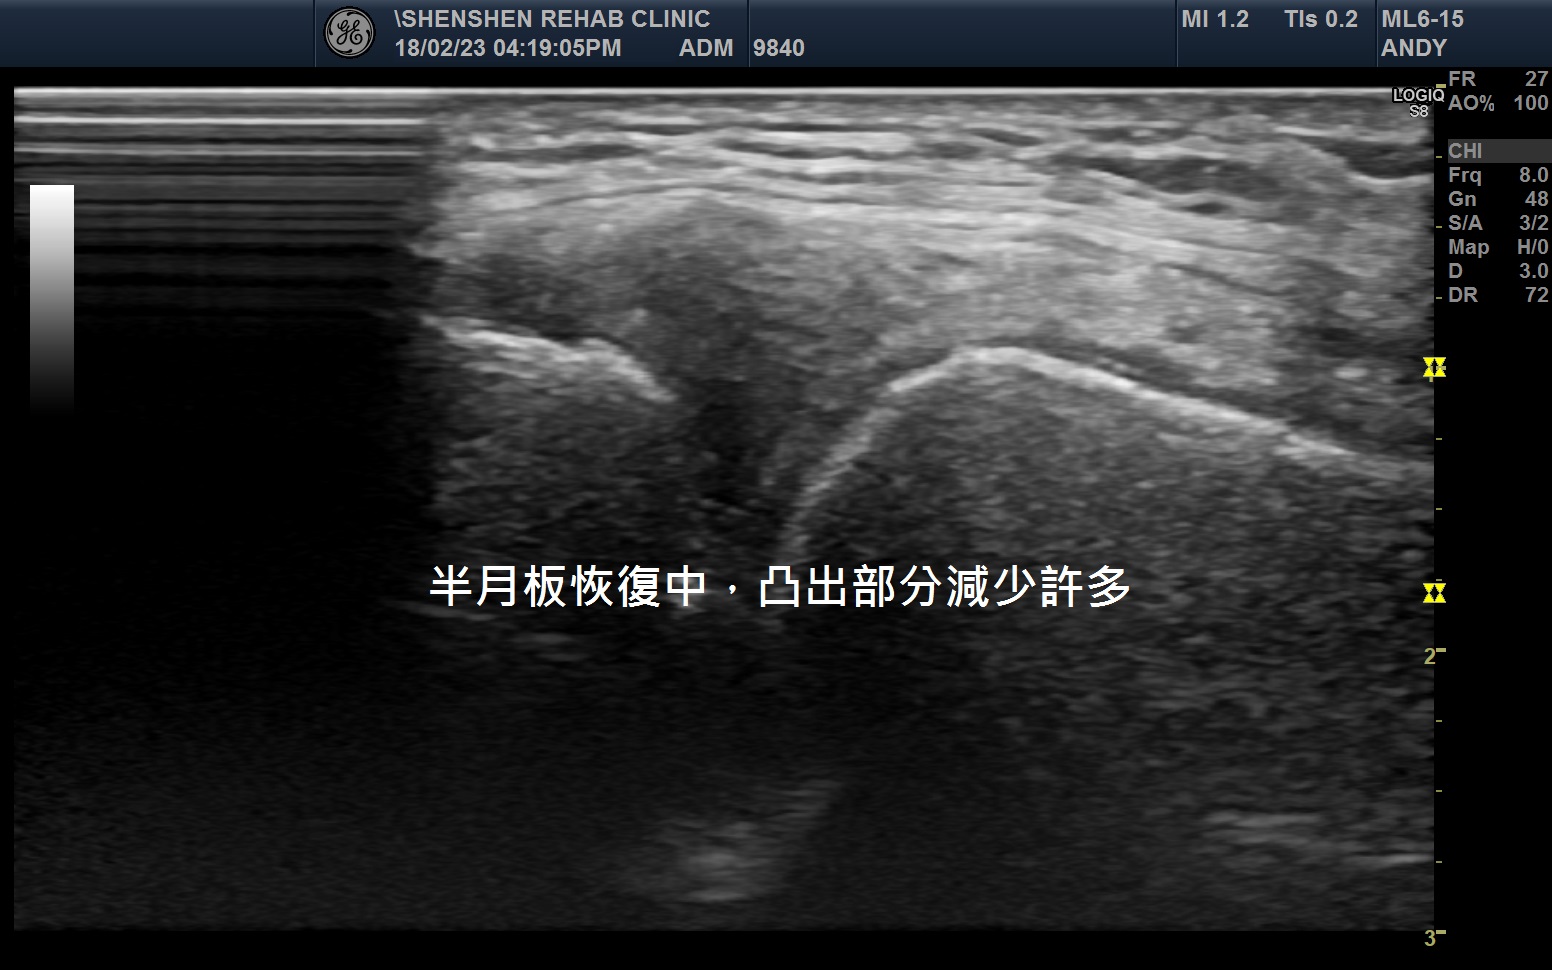

從注射完的一個禮拜開始,阿伯就發現走路症狀就日趨改善;走路的長度逐漸增加,內側膝蓋的凸起也逐漸減小。超音波檢查可發現凸出的部分縮小了。